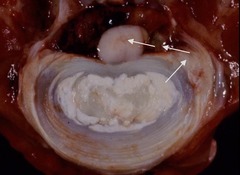

Endocardiosis

Front

Back

most common cause of congestive heart failure